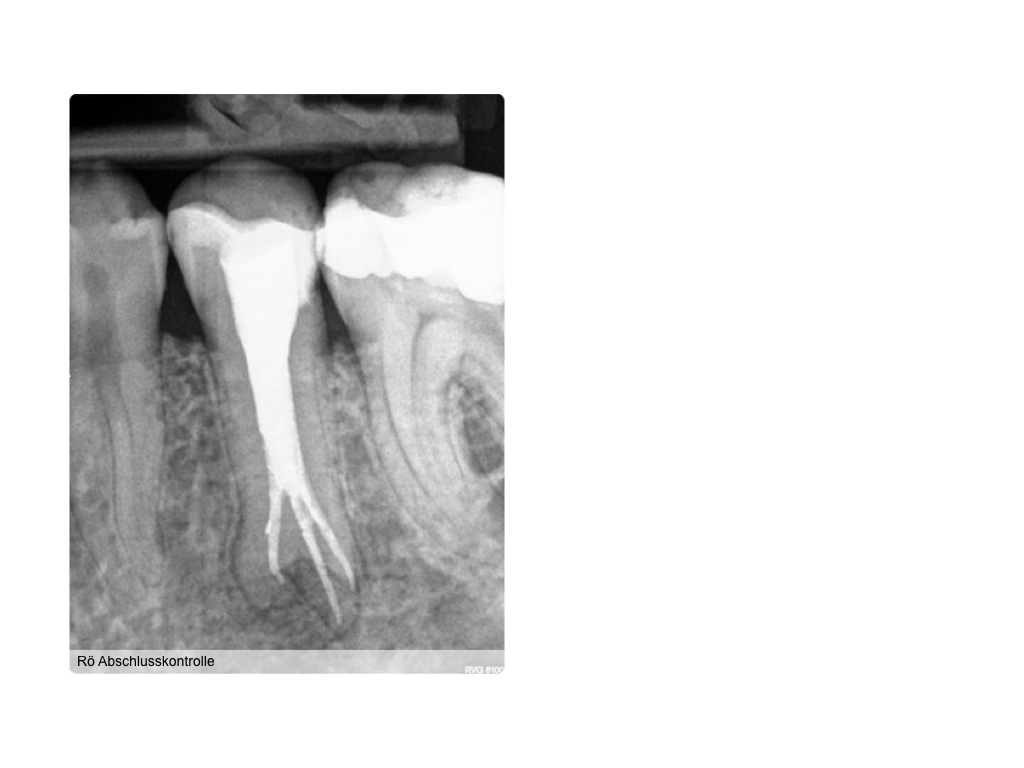

WS_Fallvorstellung15_12_2.007 Veröffentlicht 6. Dezember 2015 am 1024 × 768 in 2015 Fallvorstellung 1